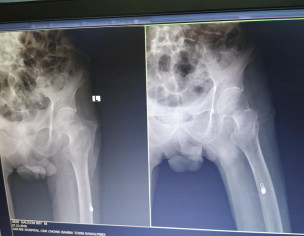

Asking for Other, Male, 90 years old, Islamabad

my grand father slipped on floor yesterday. kindly have a look on x ray i need dr opinion is this fracture is curable without surgery as his age 90 and suffering from weakness blood pressure low and no eating well please dr suggest best possible treatment

This patient needs surgery provided he would be cleared from anaesthesia department for surgery

Hi, he needs operation for this fracture to be able to walk again. Thanks

this fracture happens most commonly in old age and best solution is to perform surgery as soon possible.

if you don't get surgery, old people will suffer in bed due to complications

The best approach is to operate and mobilise him as soon as possible, because for him to be in bed is to invite very high risk.

this fracture needs to stabilize as early as possible